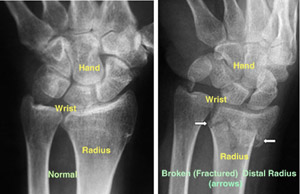

The radius is the larger of the two bones of the forearm. The end toward the wrist is called the distal end. A fracture of the distal radius occurs when the area of the radius near the wrist breaks.

DescriptionA distal radius fracture almost always occurs about 1 inch from the end of the bone. The break can occur in many different ways, however.

(Left) An x-ray of a normal wrist. (Right) The white arrows point to a distal radius fracture.